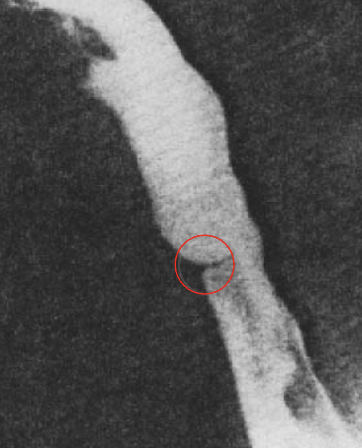

<p>What esophageal disorder is this?</p>

What esophageal disorder is this?

Benign Stricture